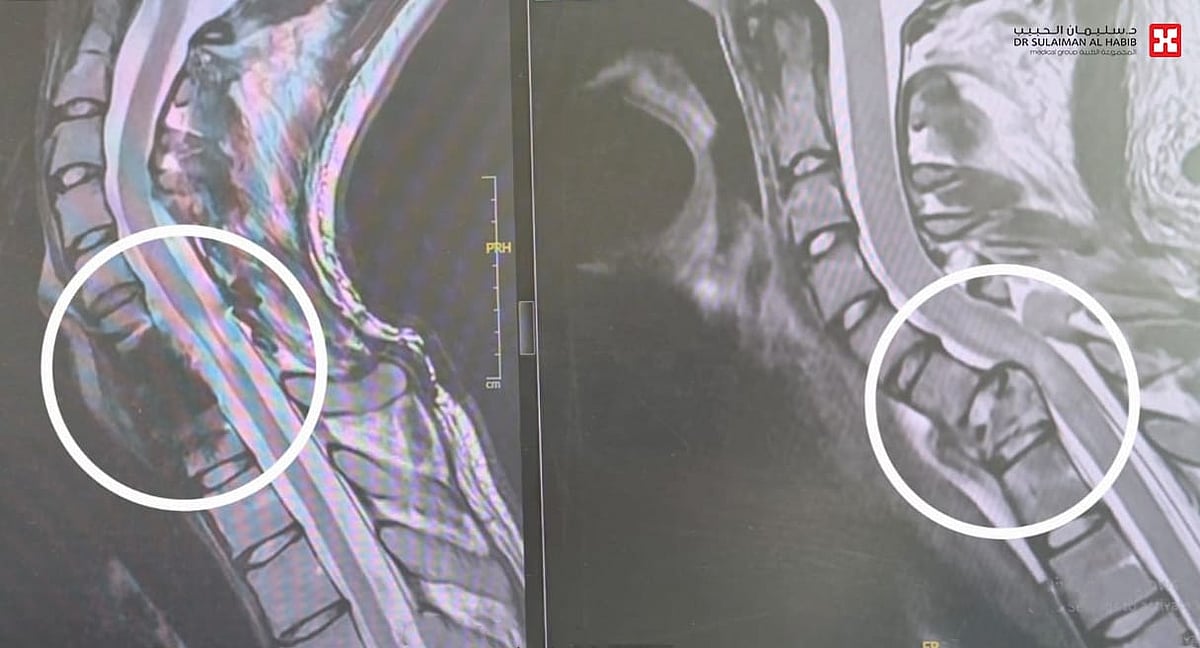

بفضل الله- تمكن مستشفى الدكتور سليمان الحبيب بالقصيم، من إنقاذ شاب تعرض لحادث مروري مروع من الشلل المحتم، وكان قد تعرض لكسر مركب بالعمود الفقري، وانزلاق غضروفي حاد أدى إلى ضغط شديد بالنخاع الشوكي، وشلل بالأطراف العلوية، وأسعف إلى طوارئ المستشفى بحالة صحية معقدة، وخضع لعمليتين دقيقتين وناجحتين لانقاذ حياته. ذكر ذلك د. ناجي مسعود استشاري جراحة المخ والأعصاب والعمود الفقري، رئيس الفريق الطبي المعالج.

وقال د. مسعود أن المصاب وهو شاب يبلغ من العمر”24″ عاماً، تلقى الاسعافات الأولية بالطوارئ ووضع على التنفس الاصطناعي مباشرة، وخضع لفحوصات دقيقة بعدما طرأ استقرار نسبي على حالته، حيث أظهرت الأشعة المقطعية Ct-scan والرنين المغناطيسي Mri وجود كسر مركب بالفقرة العنقية رقم “7”، وانزلاق غضروفي حاد وضغط على النخاع الشوكي، مع شلل في الأطراف العلوية ابتداءً من العصب رقم “7” وإلى الأسفل، وأجريت له عمليتين، تم في الأولى إزالة الفقرة العنقية السابعة المتهشمة بالكامل، والاستعاضة عنها بأخرى صناعية وتثبيتها بصفيحة وبراغي، في تدخل طبي نادر من الجهة الأمامية، وبإمكانيات كبيرة وفريق طبي متميز، واستمرت العملية لـ”5″ ساعات، وأعيد إلى العناية المركزة ووضع على التنفس الاصطناعي وبعد مرور “72” ساعة وتحسن حالته، نقل إلى غرفة العمليات مجدداً، وخضع لعملية جراحية أخرى استمرت “3” ساعات، وتم فيها إزالة الكسور المتبقية خلف العمود الفقري، وكذلك تحرير النخاع الشوكي من الضغط، تثبيت العمود الفقري ببراغي وقضبان معدنية من الفقرة العنقية 5 و6، على الفقرة الصدرية 1 و2، جرى الدخول في هذه المرة من الخلف، ونقل المصاب مجدداً العناية المركزة ووضع التنفس الاصطناعي لمدة “48” ساعة أخرى، ومع تقدم حالته، قام الفريق الطبي بتخفيف التخدير والتنفس الاصطناعي تدريجياً بطريقة تسمى weaning، وبعد “72” ساعة استفاق وبدأ في تحريك يديه، وأُحِيل إلى غرفة التنويم، واستمر تحسنه إلى أن غادر المستشفى بعد أسبوعين من العملية مشياً على قدميه مع بعض المعاونة.